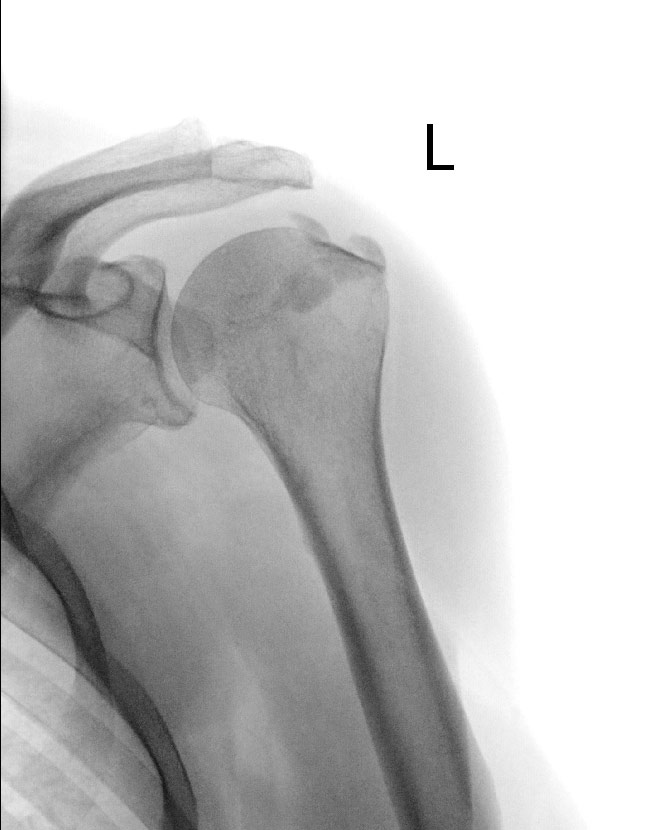

Bei der Tendinitis calcarea oder auch Kalkschulter handelt es sich um eine sehr intensiv meist nachts auftretende und schmerzhafte Erkrankung der Schulter, wobei die Sehnen der Rotatorenmanschette an der Schulter betroffen sind. Dabei ist meist die Supraspinatussehne, gelegentlich aber auch andere Sehnen der Rotatorenmanschette befallen. Es treten akute entzündlichen Beschwerden auf, welche durch eine Minderdurchblutung der Rotatorenmanschette ähnlich wie auf degenerativer Basis mit reaktiven Kalkablagerungen (Calciumhydroxyapatit-Kristalle) bedingt sind. Frauen erkranken häufiger als Männer. Die kristallinen Kalkablagerungen kann man anhand eines Röntgenbildes erkennen und somit relativ leicht diagnostizieren. Die genaue Ursache dieser Erkrankung ist weiterhin unklar, man weiss jedoch, dass kein Zusammenhang mit erlittenen Unfällen besteht.

Die Erkrankung verläuft schubweise. Die Beschwerden einer Patientin mit Tendinitis calcarea können erheblich variieren, je nach der Größe des Kalkdepots und dem Stadium der Erkrankung. Einen akuten Entzündungsschmerz erfährt der Patient während der Auflösung des Kalkdepots oder wenn das Kalkdepot in den Schulterdachschleimbeutel einbricht. Die spitzen kristallinen Kalkstrukturen führen zu einer heftigen Schleimbeutelentzündung mit stärksten Schmerzen. Allerdings finden sich in diversen Studien auch Kalkablagerungen bei Menschen ohne Beschwerden (3-20%).Sobald eine Verkalkung eingetreten ist, kann man sie mit einer Ultraschalluntersuchung nachweisen. Auch im Röntgenbild kann die Verkalkung sehr gut erkannt werden. Für die Diagnostik der Tendinitis calcarea spielt die Magnetresonanztomographie (MRT) eine untergeordnete Rolle, da das Kalkdepot sich dort nicht immer gut darstellen lässt und Verwechslungen mit einer Rotatorenmanschettenläsion (Rotatorenmanschettenriss) möglich sind.